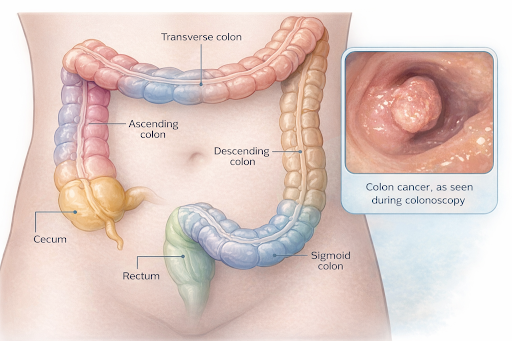

1. Overview

What is Colon Cancer?

Colon cancer is a type of cancer that develops in the colon, which is part of the digestive system. The colon helps absorb water and salts from digested food, turns waste into solid stool, and stores the stool until it is expelled from the body. Colon cancer is often grouped with rectal cancer, and together they are called colorectal cancer.

Colon cancer is a type of cancer that develops in the colon, which is part of the digestive system. The colon helps absorb water and salts from digested food, turns waste into solid stool, and stores the stool until it is expelled from the body. Colon cancer is often grouped with rectal cancer, and together they are called colorectal cancer.

2. Where It Begins

Colon cancer begins in the large intestine (colon), located in the abdomen. The colon is approximately 1.5 metres long and lies between the small intestine and the rectum.

The main parts of the colon include:

● Caecum (beginning of the colon)

● Ascending colon (right side of the abdomen)

● Transverse colon (upper abdomen)

● Descending colon (left side)

● Sigmoid colon (lower, S-shaped section)

● Rectum (final part before stool exits the body)

The main parts of the colon include:

● Caecum (beginning of the colon)

● Ascending colon (right side of the abdomen)

● Transverse colon (upper abdomen)

● Descending colon (left side)

● Sigmoid colon (lower, S-shaped section)

● Rectum (final part before stool exits the body)